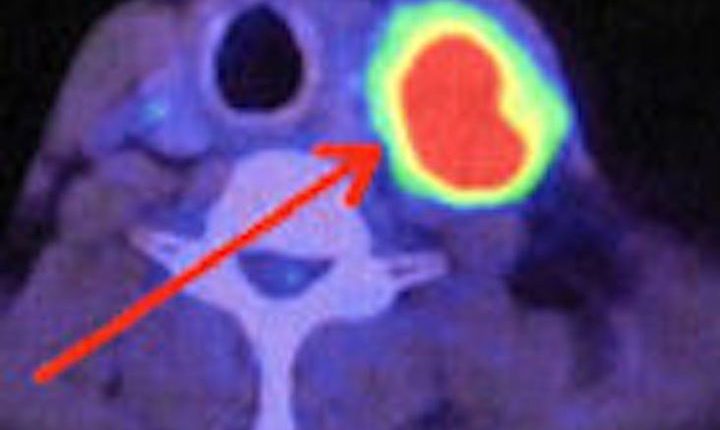

ኣዲስ ኣበባ፣ 8 መስከረም፣ 2016 (ኤፍ ቢ ሲ)ካንሰር ዝተዛብዑ ህዋሳት ብቕልጡፍ እንትከፋፈሉን ናብ ካልኦት ክፍሊ ሰውነት ዝስፋሕፋሕ ዓይነት ሕማም ኢዩ፡፡

እዞም ብቕልጡፍ ዝዓብዩ ሴላት ድማ ሕበጥ ከስዕብን ስሩዕ ተግባር ሰውነት ከዛብዑ ዝኽእሉ ኢዮም፡፡

ቀዳማይ ዓይነት ሕክምና ሕማም ካንሰር ከም መጥባሕቲ ወይ እውን ካንሰር ዝተፈጠረሉ ክፍሊ ሰውነት ወይ ሕበጥ ብምፍላይ ዝግበር ሕክምና ጨረር ኢዩ፡፡